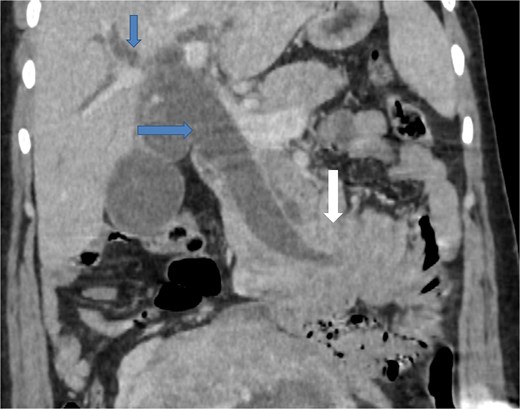

Due to the acute presentation and unavailability of emergency magnetic resonance imaging (MRI), a contrast-enhanced computed tomography (CT) scan of the abdomen was performed with strict fetal protection measures (lead apron, low-dose protocol). The pancreas appeared normal with no signs of inflammation, necrosis, or peripancreatic fluid. Unexpectedly, the scan revealed a duodenojejunal intussusception, likely originating from the fourth portion of the duodenum (D4), involving invagination of a proximal jejunal loop (Fig. 1). A typical pseudokidney sign was observed on sagittal reconstructions (Fig. 2). There was no identifiable lead point such as a mass or polyp. The intussusception was seen tractioning the distal common bile duct, leading to marked extra- and intrahepatic bile duct dilatation (Fig. 3).

Coronal contrast-enhanced CT image showing the intussusception causing traction on the distal common bile duct (arrow at the bottom), resulting in significant upstream dilatation of the extrahepatic and intrahepatic bile ducts (two arrows at the top).